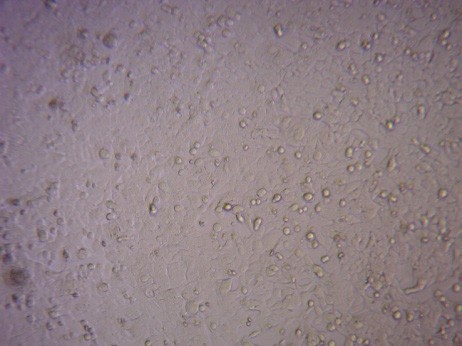

Finally, to analyse the cytotoxic activity of the Green synthesized FMCuNPs, we performed MTT assay with two well-established cancerous cell line HepG2 and MCF-7. The greenly synthesized FMCuNPs had IC50 values of 57.56 µg/ml for HepG2 cell line and 56.41 µg/ml for MCF-7 cell line (fig. 17 and table 4). The comparative study of morphology alteration of the cell line in response to the treatment with FMCuNPs is also depicted in fig. 18. Thus our data showed that FMCuNPs has exerted a promising and selective cytotoxic activity against both HepG2 and MCF-7 cell line.

![]() |

n=3, mean±sd |

Fig. 17: Cytotoxicity of FMCUNPs on HepG2 and MCF-7 cells

Fig. 18: Morphological changes in HepG2 and MCF-7 Cell lines